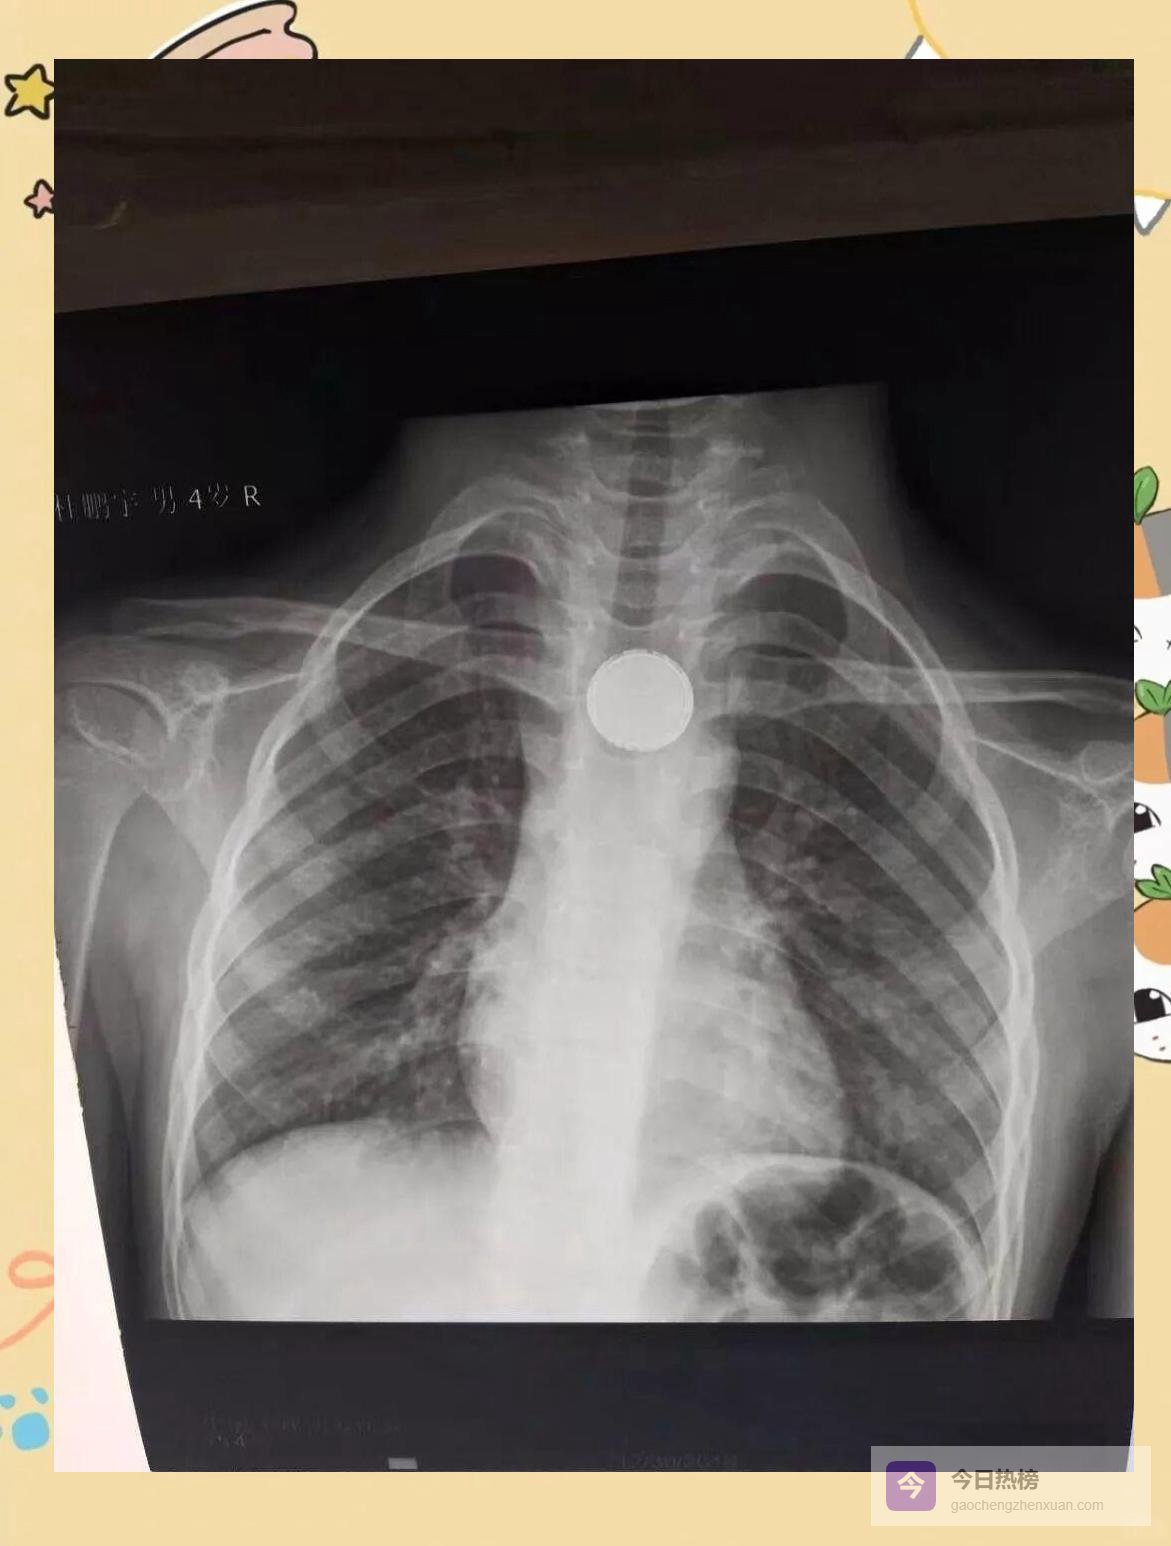

3.1 ❒ 假期首日,异物榜单刷新仅元旦上午, “绿色通道”就紧急介入5例吞食异物患儿:不到1岁的婴儿误吞纽扣电池,7岁女孩枣核卡喉,还有指甲刀、硬币……每一例都可能演变为消化道穿孔或化学性灼伤。

3.2 ❒ “有惊无险”背后的高强度协作 内镜中心、麻醉科、手术室无缝衔接:钳取、剥离、探查,每一分钟都在与腐蚀性损伤赛跑。孩子哭声停歇,家长泪光闪动,一句“谢谢”被反复说出,成了医护最动听的“新年彩蛋”。